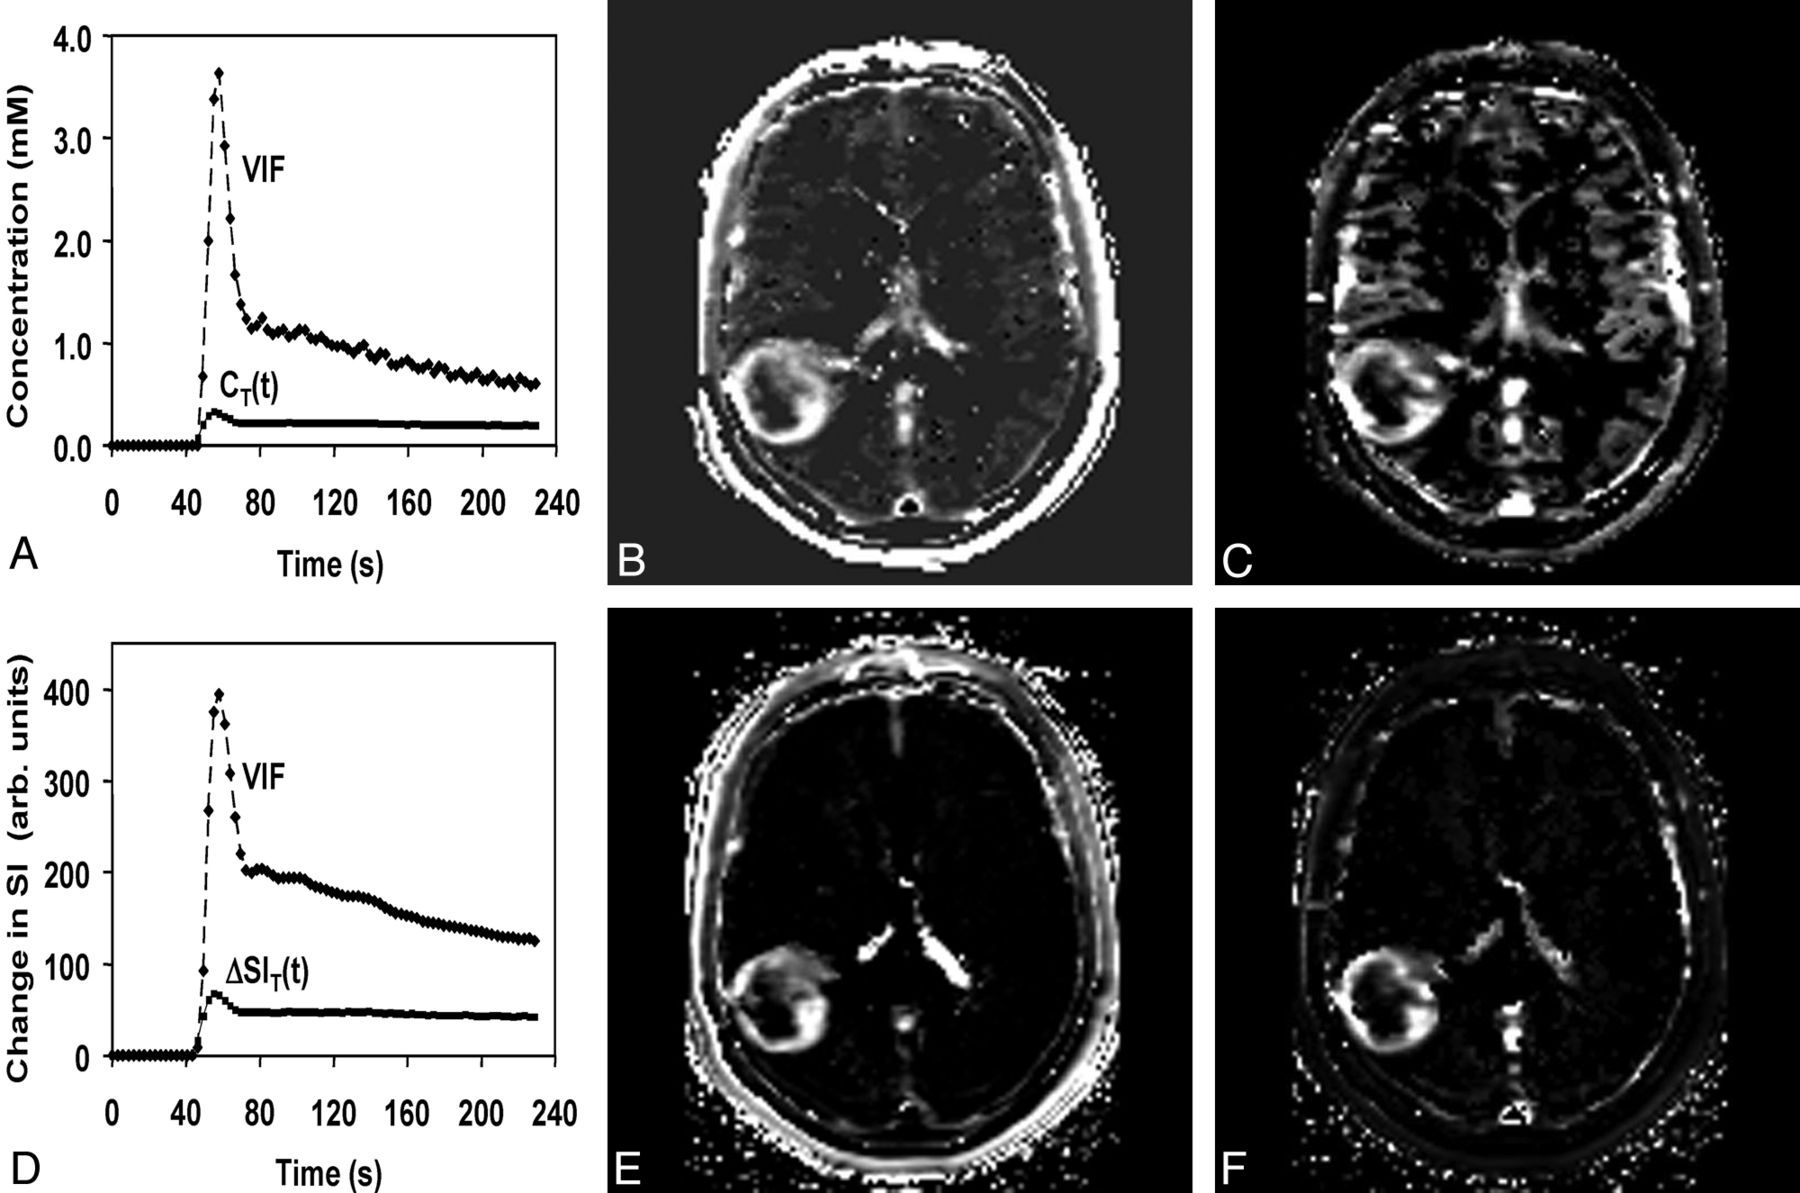

Voxel wise maps of CT(t) were calculated in 2 steps. First, the double echo was used to extrapolate all magnitude signals to TE = 0 ms, thereby reducing T2* effects. Second, the pre- and post-DCE T1 maps were combined with the extrapolated tissue signal-intensity-versus-time curve by using standard signal-intensity equations to compute CT(t). The VIF was calculated from the superior sagittal sinus by measuring the change in phase as a function of time, taking into account the angle of each vessel segment relative to the main magnetic field. This step was performed off-line by using in-house software written in IDL (ITT Visual Information Solutions, Boulder, Colorado) and is described in a previous article.8 Voxel-by-voxel estimates of Vp_ϕ and Ktrans_ϕ were determined by using a kinetic model analysis from the nordicICE software (Version 2; NordicNeuroLab, Bergen, Norway) as described in the Appendix. Representative parametric maps of Vp_ϕ and Ktrans_ϕ are shown in Fig 1B, -C.

A, Phase-derived VIF and tumor CT(t) from a patient with confirmed grade IV glioma obtained at 3T. B and C, Ktrans_ϕ (B) and Vp_ϕ (C) maps. D, Magnitude-derived VIF and tumor signal-intensity changes from the same patient for comparison. E and F, Ktrans_SI (E) and Vp_SI (F) maps. Maximal Ktrans_ϕ and Vp_ϕ values in tumor are 0.099 minutes−1 and 5.7 mL/100 g compared with 0.15 minutes−1 and 18 mL/100 g for Ktrans_SI and Vp_SI.

DCE magnitude images were processed directly in Nordic ICE to generate maps of Vp_SI and Ktrans_SI as described in the Appendix (Fig 1D, -E).